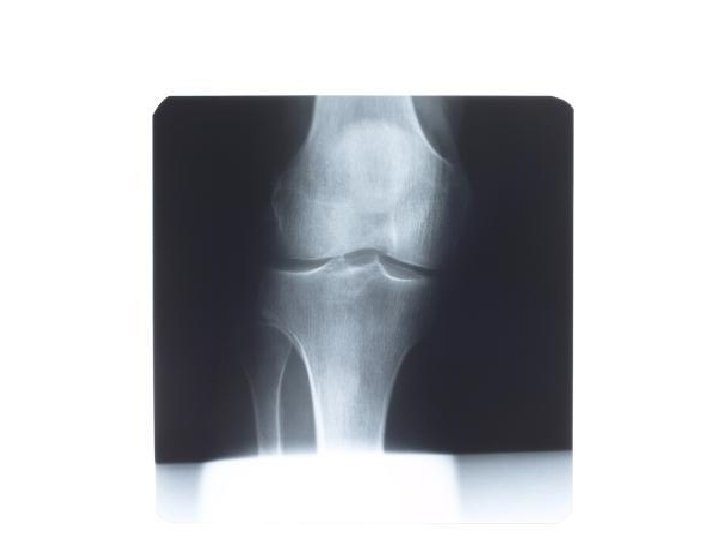

Hinge Flexion/Extension e. g tibiofemoral joint